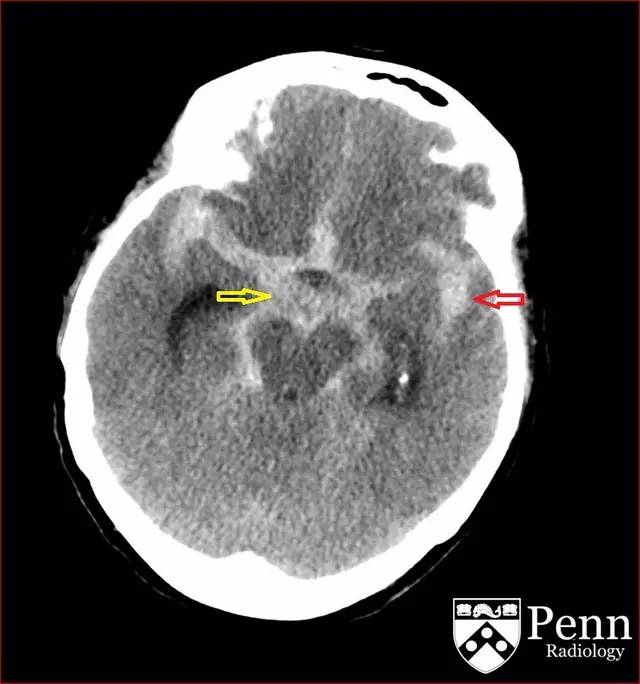

图 1 平扫 CT 可见广泛的蛛网膜下腔出血,累及基底池(黄色箭头)、外侧裂(红色箭头)

图 2 平扫 CT 可见广泛的蛛网膜下腔出血,累及基底池(黄色箭头)、外侧裂(红色箭头)

CT 可见广泛的蛛网膜下腔出血,累及基底池、外侧裂并延伸到额叶。